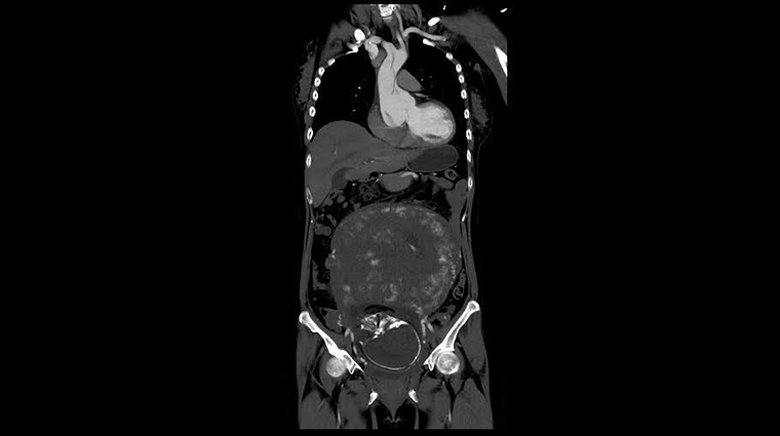

孕婦併發急性主動脈剝離的案例極少見,若伴隨先天性主動脈血管壁異常,風險將大大提升。(圖/台北慈濟醫院提供)

36歲劉小姐懷孕9個月,日前無預警劇烈胸痛、瀕臨休克,被緊急送至台北慈濟醫院急診。經心臟外科蔡貴棟醫師診斷其患有7公分大的主動脈根部動脈瘤,因主動脈瘤內膜裂開導致A型主動脈剝離。

為全力保住母子倆,蔡貴棟醫師與醫療團隊審慎評估,孕婦幼年時期曾做過主動脈瓣膜修補手術,術後沾黏或可延遲主動脈剝離的出血時間,因此決定先取出胎兒,而後執行升主動脈及主動脈根部動脈瘤置換手術。手術時間逾16小時,術後劉小姐入住加護病房觀察待病情穩定後,轉至普通病房復健1周,出院後定期回診追蹤,順利回歸原有家庭生活。

蔡貴棟醫師指出,主動脈剝離發生率約每年每10萬人口的2到2.5個百分比,好發於動脈硬化、三高、肥胖、先天性結締組織病變患者,「另外,孕婦在第3產程時,受胎兒成形影響會增加20%的母體心臟輸出量,併發主動脈剝離的風險是同齡無懷孕女性的4倍。」主動脈剝離典型症狀為劇烈性胸痛,可依病灶分為A型、B型兩種。A型主動脈剝離因侵犯到主動脈弓、升主動脈,死亡率以病發當下每小時1-2%累計,且一旦主動脈根部破裂,將造成休克、心包膜填塞死亡,需立即手術;而B型主動脈剝離侵犯到降主動脈,可先以藥物控制。

孕婦併發急性主動脈剝離的案例極少見,若伴隨先天性主動脈血管壁異常,風險將大大提升。而如劉小姐情形,幼兒時期因主動脈瓣逆流做過主動脈辦膜修補手術,且於日後罹患7公分大的主動脈根部動脈瘤,更加劇主動脈剝離的危險性。台北慈濟醫院心臟外科團隊審慎評估,其先前做過心臟手術,所形成的沾黏或可延緩心包膜填塞產生時間,即與婦產科合作先進行剖腹產手術,確保無產後出血等症狀後再計畫執行主動脈剝離手術。

產後的修復期間,劉小姐病情急遽惡化,2度瀕臨死亡,醫療團隊緊急為其裝置葉克膜體外循環心肺支持系與人工心肺機,而後針對劉小姐的主動脈根部動脈瘤及主動脈剝離2種病症,執行逾16小時的升主動脈及主動脈根部動脈瘤同時置換手術。